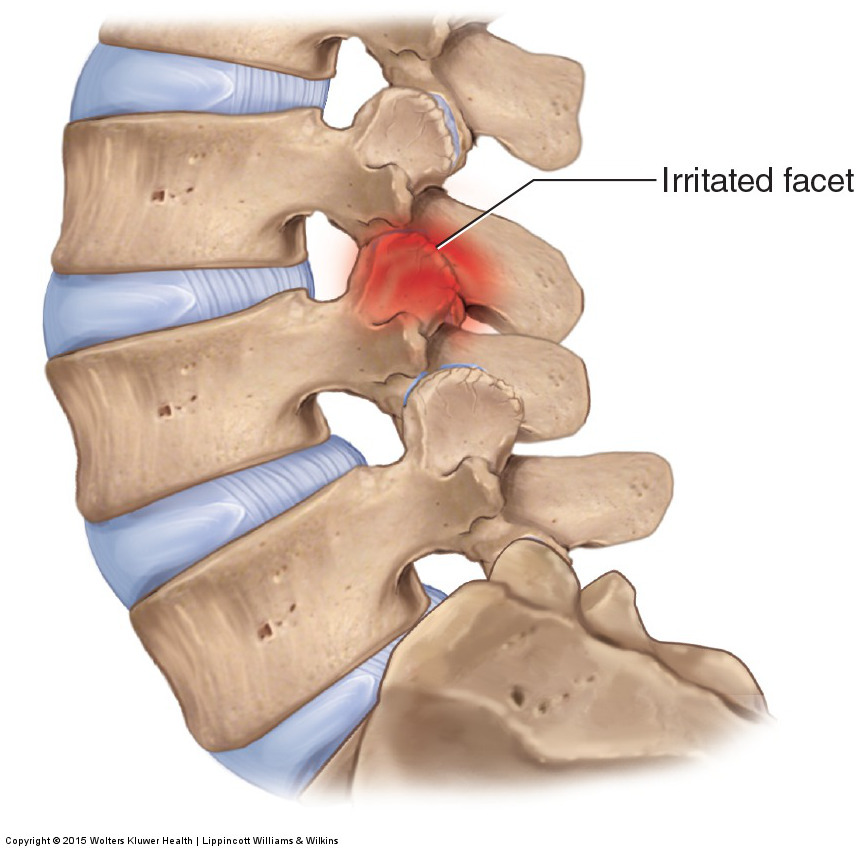

Остеоартрит фасеточных суставов: медицинские снимки и схемы